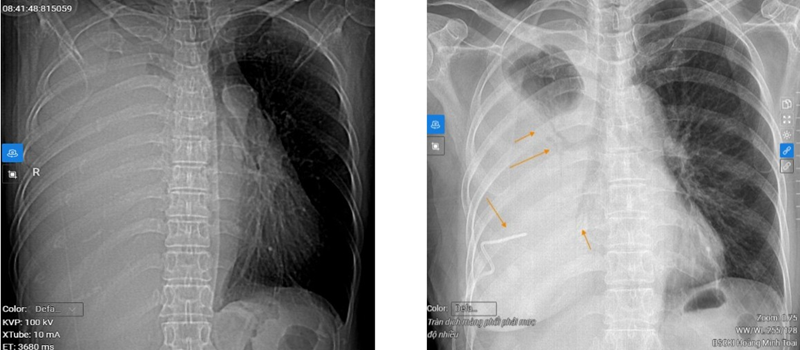

Chụp CT phổi cho thấy hình ảnh tràn dịch màng phổi phải mức độ nhiều, đè ép xẹp hoàn toàn nhu mô phổi, đẩy tim và trung thất lệch trái. Nốt đặc phổi trái phân thùy S6 sát trung thất kích thước 10x15mm, bờ đều, ranh giới rõ, bên trong có tỷ trọng vôi (103 HU) (phân loại Lung RADS 4X – nghi ngờ ác tính cao).

Hình ảnh tràn dịch khoang màng phổi phải mức độ nhiều và nốt đặc phổi trái phân thùy S6 sát trung thất

Hình ảnh trước khi dẫn lưu dịch màng phổi (ảnh trái) và sau khi dẫn lưu 1.000ml dịch màng phổi